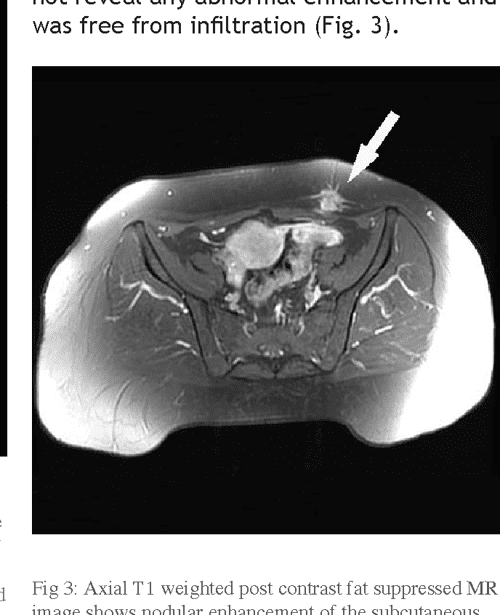

From radiopaedia.org

Scar endometriosis Image Scar Endometriosis Treatment In Homeopathy Sanchita dharne, recognized as the best homeopathic doctor in gurgaon, is an expert in treatment of endometriosis with homeopathy. in short, while conventional treatments for endometriosis focus on immediate symptom relief and hormonal management, the homeopathic. in the fight against endometriosis, homeopathy offers a number of specific remedies designed to relieve. Homeopathic medicines for endometriosis are primarily intended. Scar Endometriosis Treatment In Homeopathy.